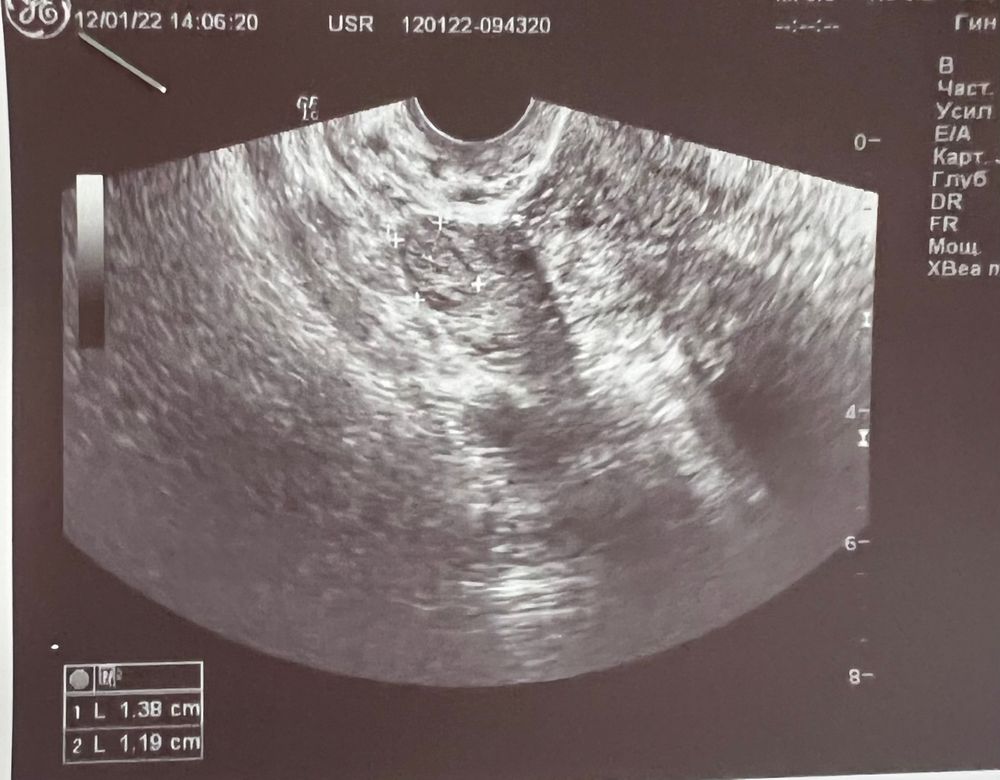

сегодня сделала фолликулометрию, посмотреть, есть ли желтое тело. Врач узи ооочень сомневалась, что это именно желтое тело, еле еле его нашли.

Фолликул в вс был 22 мм, в пн тест на овуляцию был положительным, сегодня среда, фолликула уже нет. Но он мог и сдуться( в общем, посмотрите, пожалуйста, кто понимает в узи, видите ли вы желтое тело?(

Анастасия Романова, ЖТ анэхогенное, это образование эхогенное, больше похоже на сморщенный фолликул. Сдайте прогестерон, сразу будет понятно

Софья, узи делала в инвитро, там врачи часто косячат. Отправила фото своему лечащему врачу, она меня успокоила) говорит, что все в норме, жт она тоже видит, просто померили его странно) а на будущее, как сдавать анализ на прогестерон, какие результаты свидетельствуют об овуляции?)